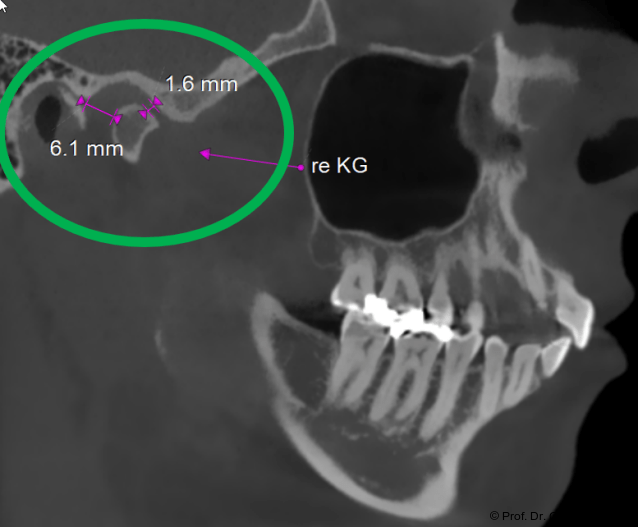

Im Sagittalschnitt zeigen beide Kiefergelenke eine deutlich anteriore Position. Der dorsokraniale Abstand betrug rechts 7,0 mm und links 5,8 mm. In der PEP waren sie im lateralen Bereich ca. 1 mm kleiner als in der Mitte der Sagittalprojektion (Abb. 6a–d).

Exakter ist jedoch die Bestimmung des zentralen Wahrnehmungs­ortes des Gleichgewichtsorgans, der Macula sacculi. Diese befindet sich im Sacculus vestibularis der jeweiligen Seite. Die Mitte der Linie zwischen dem Sacculus vestibularis dexter und sinister ist dann der ursprüngliche Nullpunkt der CranioPlan-Analyse. Dieser Punkt liegt etwas posterior zur Mitte der Hammerknöchelchen und gibt den exakten OriginPoint (O-Punkt) als Ausgangspunkt der afferenten Sym­metrieachse an (Abb. 22–24).